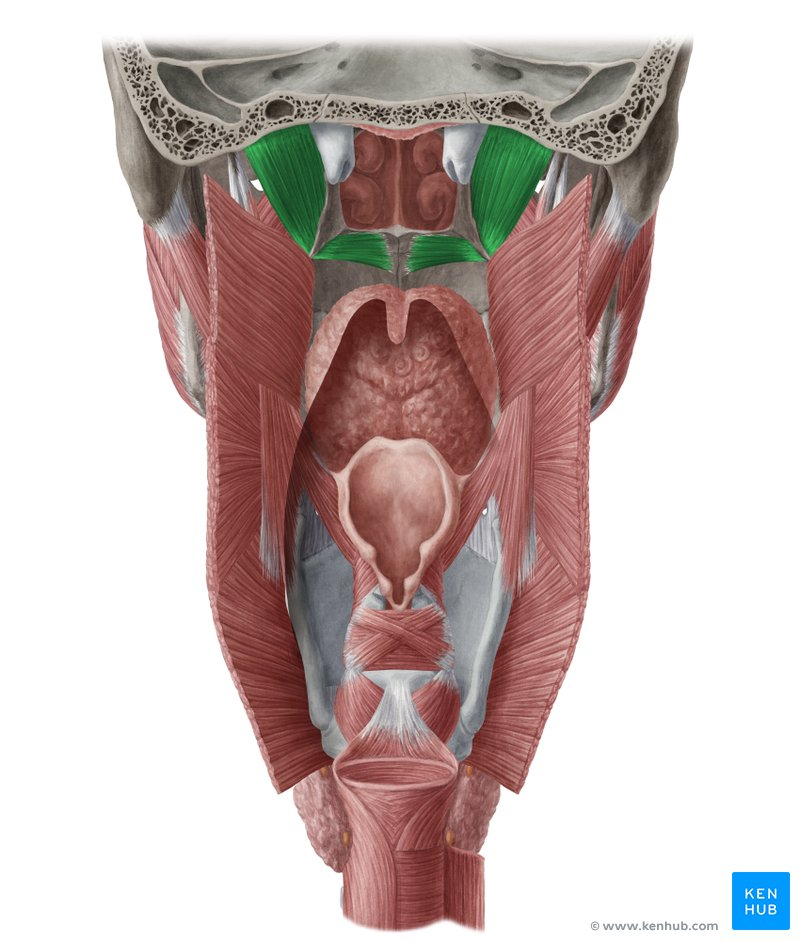

Name #3

Levator veli palatini m.

Name the structure

Torus levatorius

Tensor veli palatini m.

Salpingopharyngeus m.

Name #4

Salpingopharyngeal fold

Palatoglossus m.

Palatoglossal arch / fold (anterior fauces)

Palatopharyngeus m.

Name #2

Palatopharyngeal fold (posterior fauces)

Stylopharyngeus m.

Name #6

Superior pharyngeal constrictor m.

Name #5

Middle pharyngeal constrictor m.

Inferior pharyngeal constrictor m.